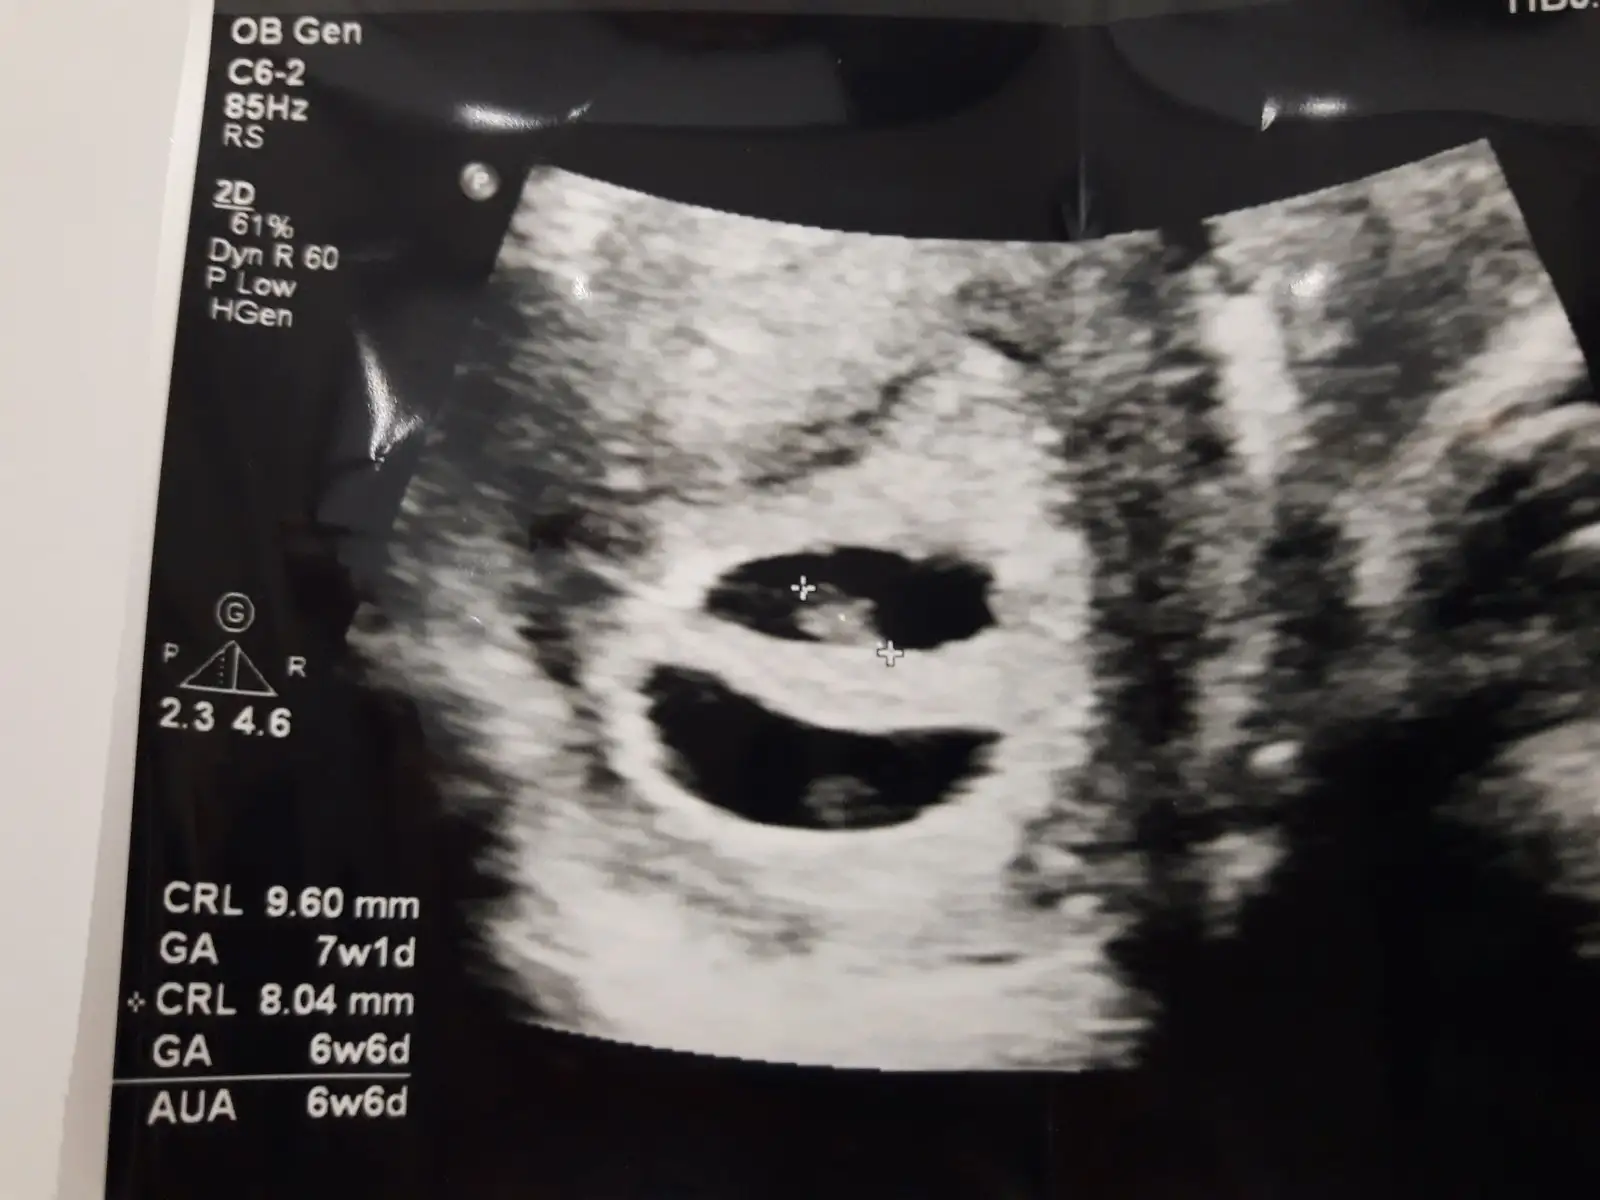

Oyy maşallah yaaa, ne sevimliler. Kucagına aldığın zamanları da görün inşallah. Çok tatlılar 7+1gösterıyorla. Yani 8. Haftanın içindesinEki Görüntüle 2212178 Eki Görüntüle 2212179 teyzeleri bunlar minnaklar. Video cek dedim esime bizeye benzediklerinde cekeriz dedi tamda doktor geldi uzatamadim mevzuyu.![]()

Bende onu sorucaktim doktora nasillar dedim fistik gibiler dedi guldu. Biri 7+1 biri 6+6 gosteriyo. Normalde bakinca 6+4uz bugun. Yemisler beni simdidenOyy maşallah yaaa, ne sevimliler. Kucagına aldığın zamanları da görün inşallah. Çok tatlılar 7+1gösterıyorla. Yani 8. Haftanın içindesin![]()

Maşallah canım, gelişimleri iyi demek ki :)Bende onu sorucaktim doktora nasillar dedim fistik gibiler dedi guldu. Biri 7+1 biri 6+6 gosteriyo. Normalde bakinca 6+4uz bugun. Yemisler beni simdidenbiri 2 gun biri 4 gun onde masallahhhh kuzulara